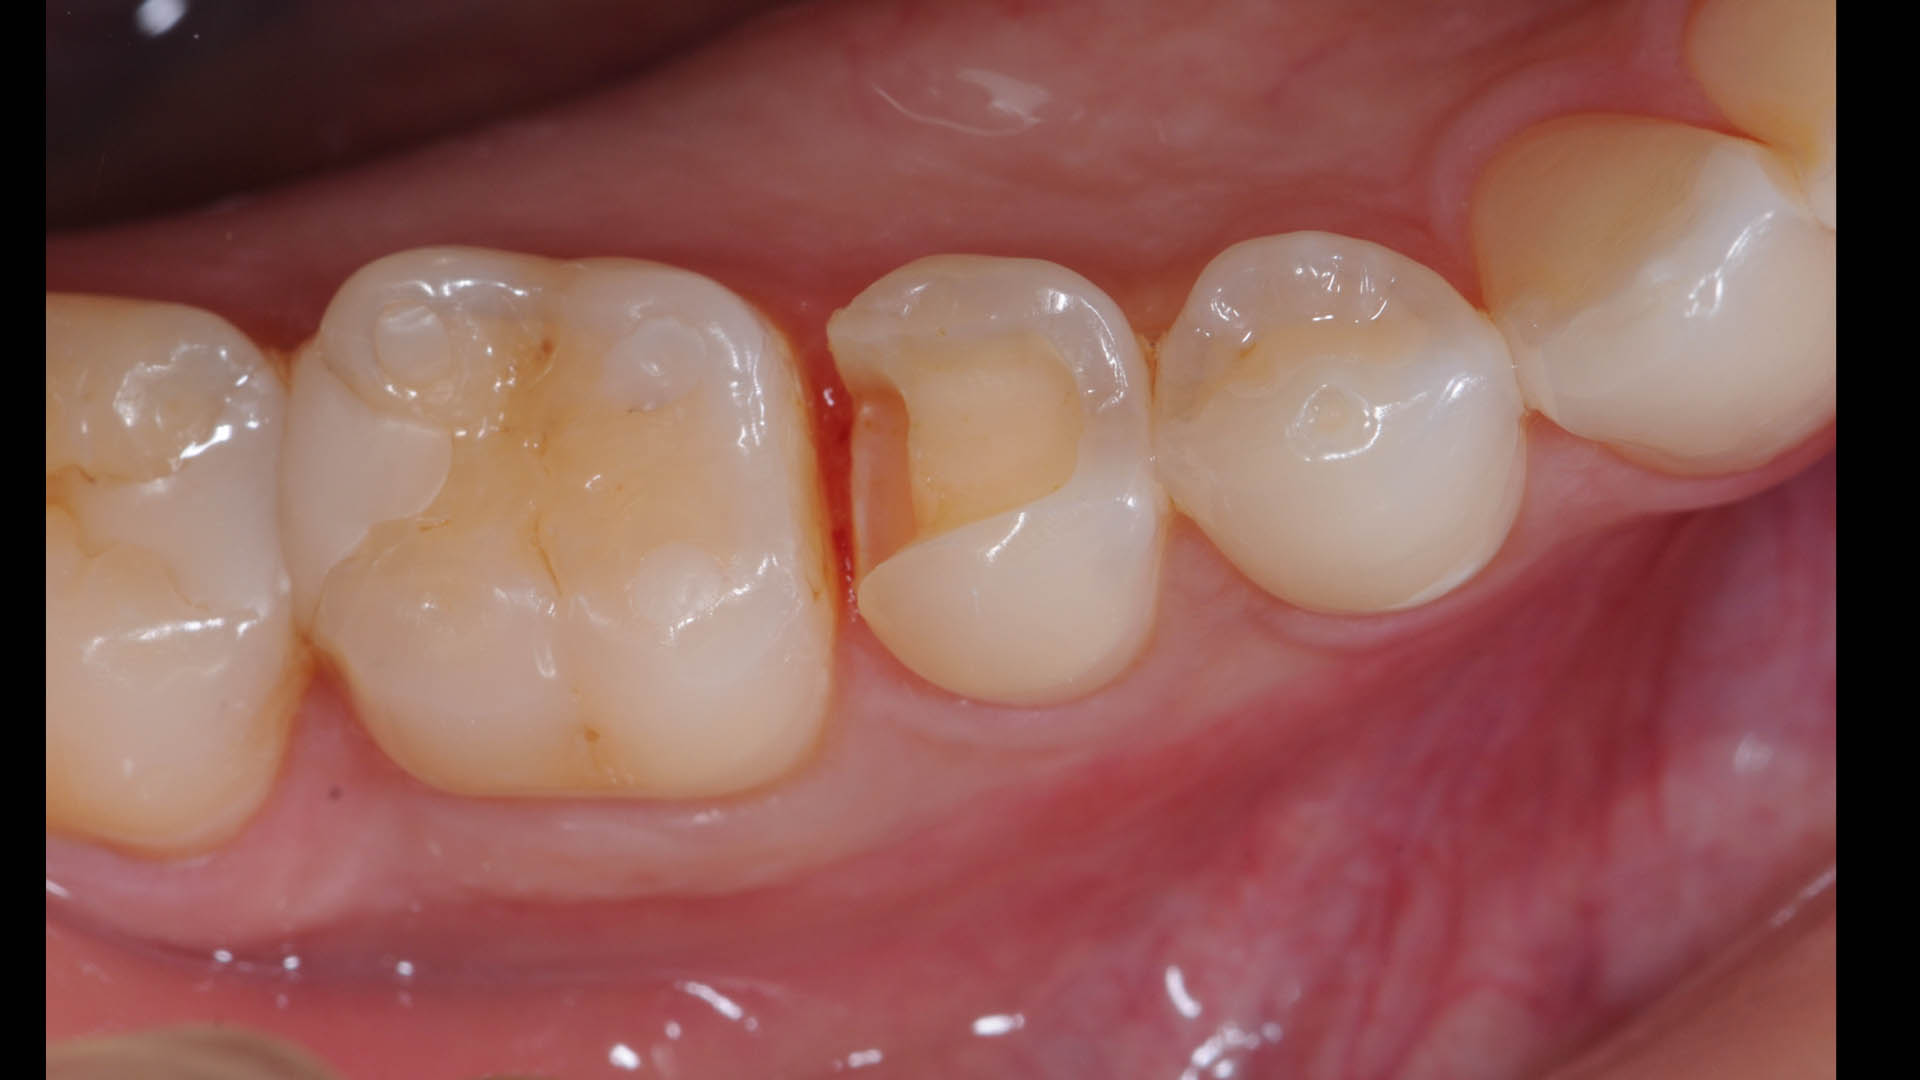

Take a glimpse into the magic of Coral Gables Dentistry through our before and after pictures. See firsthand the incredible smile makeover transformations that have brought confidence and joy to our patients.